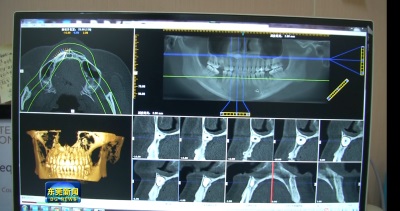

活动期间,许多缺牙患者也抓住本次“爱美月”的种植牙福利,前往东莞口腔医院拍片检查,找到专业强大的种植团队为他们分析口腔情况,设计种植牙方案。参与的市民都称赞道,虽然是免费的,但医生问诊绝不马虎,非常细心地向他们解释种植牙方案,也向他们科普了种植牙的相关知识,体验感很棒!

“爱美月”活动也吸引了东莞广播电视台走进东莞口腔医院跟踪报道。正畸科左雷医生和种植科金熙凡医生皆向媒体记者谈到,正畸和种植牙修复对改善口腔健康状况,从而促进全身健康是有重要作用的,但很多人因为各种原因耽误了看牙。我院举办“爱美月”这一个活动也是想告诉广大市民有时间、有机会就赶紧去看牙了,重要的就是“早”!也希望通过这样的宣传活动引起人们对口腔健康的关注,一起爱牙、护牙。